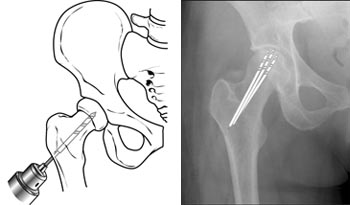

(Left) Core decompression. (Right) In this x-ray, the drill lines show the pathway of small drill holes used in a core decompression procedure.

This procedure involves drilling one larger hole or several smaller holes into the femoral head to relieve pressure in the bone and create channels for new blood vessels to nourish the affected areas of the hip.

When osteonecrosis of the hip is diagnosed early, core decompression is often successful in preventing collapse of the femoral head and the development of arthritis.

Core decompression is often combined with bone grafting to help regenerate healthy bone and support cartilage at the hip joint. A bone graft is healthy bone tissue that is transplanted to an area of the body where it is needed.